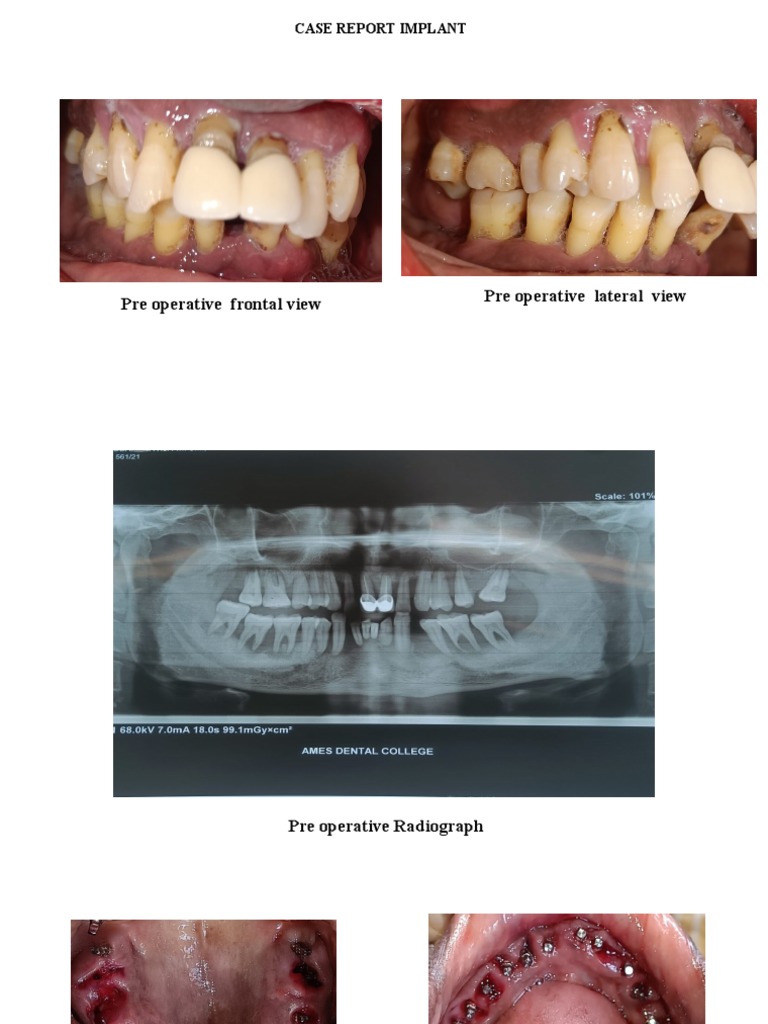

Immediate Anterior Dental Implant PlacementA Case Report Case Report Implant Dentistry case reports in dentistry is an open access journal that publishes case reports and case series in all areas of dentistry, including. the aim of this case report is to illustrate how digital profiles of a patient’s facial and intraoral features can be merged. Tooth loss among adults is associated with progressive periodontitis. lichen planus (lp) is. Case Report Implant Dentistry.